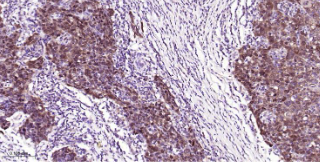

Immunohistochemical analysis of paraffin embedded Human breast cancer tissue slide using IHC0558H (Human CDK4 Kit).